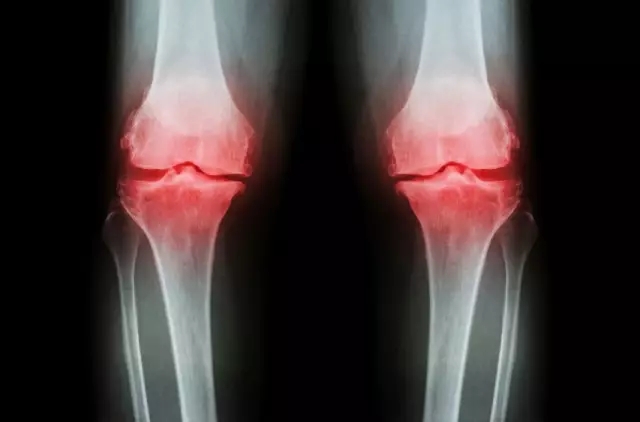

病理性的关节弹响是由于关节的损伤、疾病或结构的变异,致使滑膜粗糙,关节囊、韧带松弛,肌腱增生或腱鞘狭窄,关节盘破裂,关节软骨脱落等,在运动时就会因上述组织的摩擦而产生弹响。

病理性关节弹响的响声可以是清脆的、沉闷的或磨砂样的,多数伴有疼痛或不适感,并且都是可以连续发生的。

常见的有膝关节骨性关节炎,膝关节内骨赘(俗称骨刺)断裂形成关节内可以移动的小骨块,手指部位狭窄性腱鞘炎等。

例如:膝关节内半月板破裂,行走出现弹响;伤及关节部位的骨折,术后关节软骨面不再光滑,变得凹凸不平,关节转动不顺畅,活动时出现响声。

病理性弹响主要是关节软骨、关节滑膜等结构发生异常所引起的,但这类原因导致的弹响只是临床表现的一部分。当出现关节退化、病变,如髌骨软化症、关节软骨损伤、半月板撕裂、关节脱位等情况时。

关节发出的声音的同时通常伴有其它症状及病理变化,如伴有疼痛、肿胀、关节活动受限甚至运动异常。此时就需要尽快到医院就诊,并确定是否是关节错位或关节受损,以免耽误治疗。